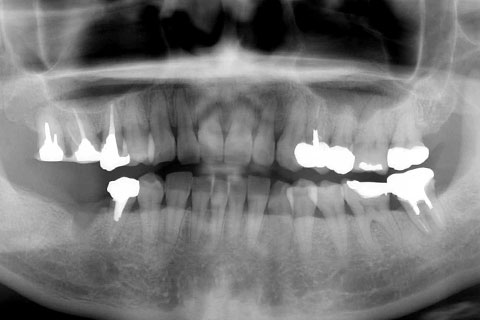

症例2

治療前

インプラント埋入時

治療後

- 年齢・性別

- 57歳男性

- 治療期間

- 3ヶ月

- 抜歯

- なし

- 治療費

- 154万円

- 備考

- 左上5.6.7 及び左下6.7欠損

- 治療内容

- 左上5.6.7と左下6.7欠損部にインプラント埋入

- 施術の副作用(リスク)

- オペによる知覚障害。インプラントによる歯肉炎。インプラント脱落。